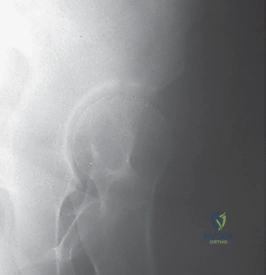

صور إضافية لخطوات الجراحة الدقيقة والمتابعة الإشعاعية

يوثق الأستاذ الدكتور محمد هطيف كل خطوة جراحية لضمان أعلى معايير الجودة والشفافية الطبية.